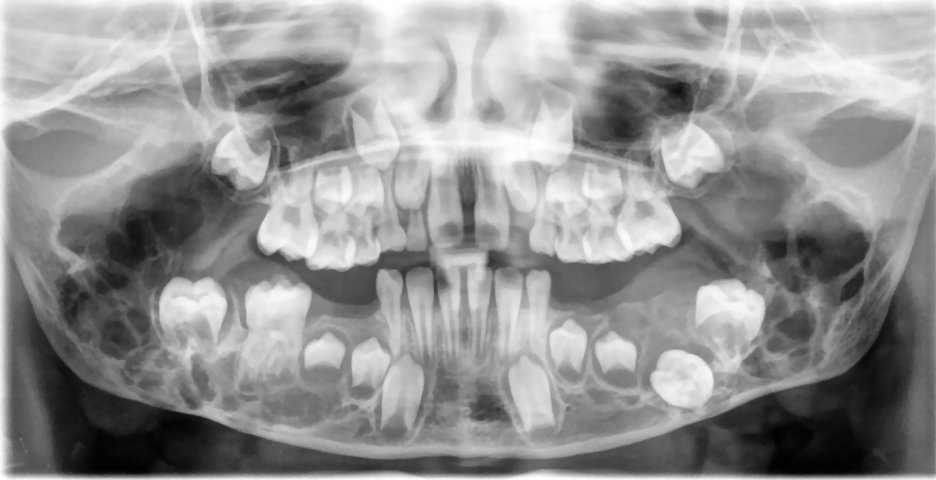

Χερουβισμός .

- Είναι κληρονομική νόσος.

- Κλινικά προκαλεί αμφοτερόπλευρη διόγκωση του προσώπου σε παιδιά. Η διόγκωση μεγαλώνει προοδευτικά χωρίς να προκαλείται πόνος.

- Ακτινογραφικά απεικονίζεται πάντα σαν αμφοτερόπλευρη πολύχωρη διαύγαση στον κλάδο και στο σώμα της κάτω γνάθου ή ακόμη και στην άνω γνάθο.

- Συνήθως έχει σαφή και καλά καθορισμένα όρια.

- Μπορεί να προκαλέσει σημαντική παρεκτόπιση, εγκλεισμό και απορρόφηση ρίζας των γειτονικών δοντιών.

- Η νόσος με την πάροδο της ηλικίας υποστρέφεται.